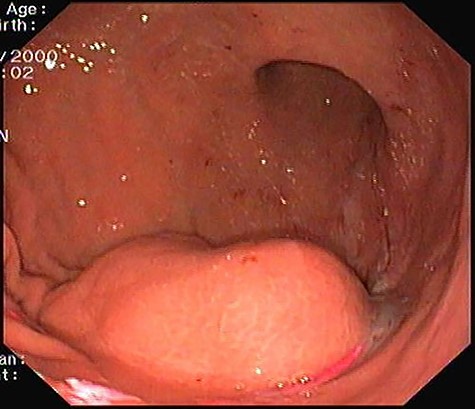

Upper gastrointestinal endoscopy: 4 cm subepithelial lesion located at gastric antrum.

Presenting an initial clinical picture of epigastric pain and nonspecific dyspeptic symptoms, the patient underwent upper gastrointestinal endoscopy (Fig. 1) where a subepithelial lesion was found, mandating further investigation. Endoscopic ultrasonography (Fig. 2) arose suspicion of GIST and computed tomography scan (Fig. 3) revealed an exophytic lesion with 97 × 77 × 57 mm rising from the gastric greater curvature, with no signs of metastatic or locally advanced disease.